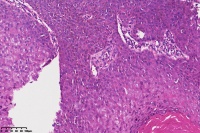

脂溢性角化症伴皮角?

女

年龄

49岁

手臂皮肤组织

图3

脂溢性角化病